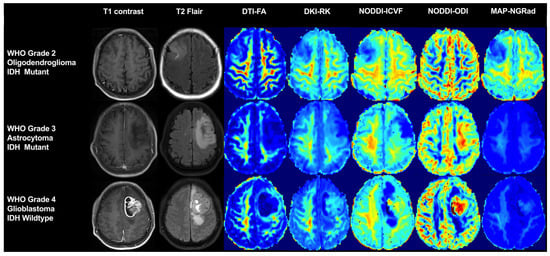

4.2.2. Multiple Diffusion Model Imaging (DXI)

Diffusion-weighted imaging (DWI) and diffusion tensor imaging (DTI) are the only techniques employed for the in vivo measurement of water molecule dispersion motion. Recently, DXI has emerged as a comprehensive approach that facilitates the acquisition of various diffusion models from a single scan (Figure 3), encompassing DTI, diffuse kurtosis imaging (DKI), mean apparent propagator (MAP) MRI, and neurite orientation dispersion and density imaging (NODDI). The aforementioned models have demonstrated exceptional performance in accurately predicting glioma genotyping [75] and effectively distinguishing GBM from isolated brain metastases [76].